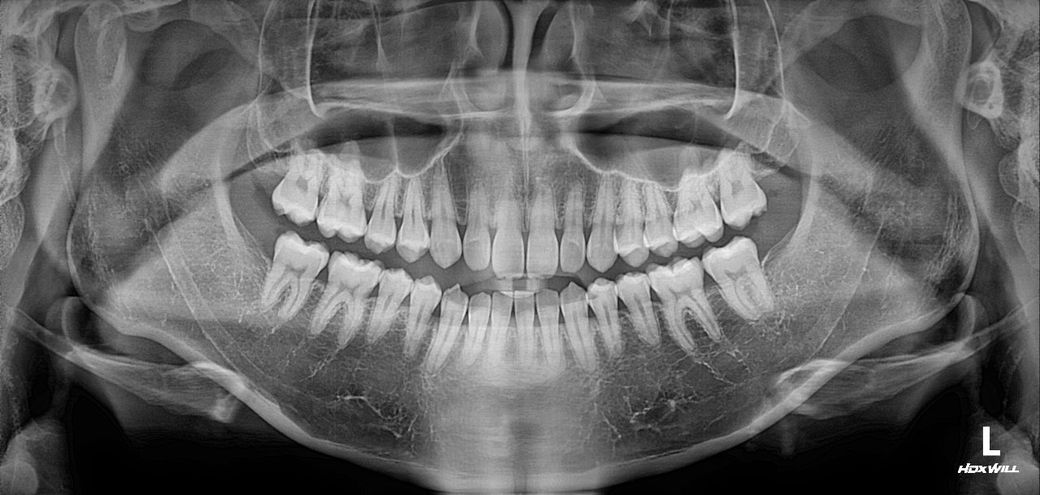

질문3. 제 앞니 치근이 짧나요?

앞니 치근은 짧은편으로 보입니다.

3. 정상범위에 속합니다.

-절대적인 기준은 없지만 파노라마 상으로만 본다면 치근이 짧아보입니다

오른쪽 앞니 두번째 치아의 반대교합을 제외하면 치열이 거의 정상에 가깝습니다.